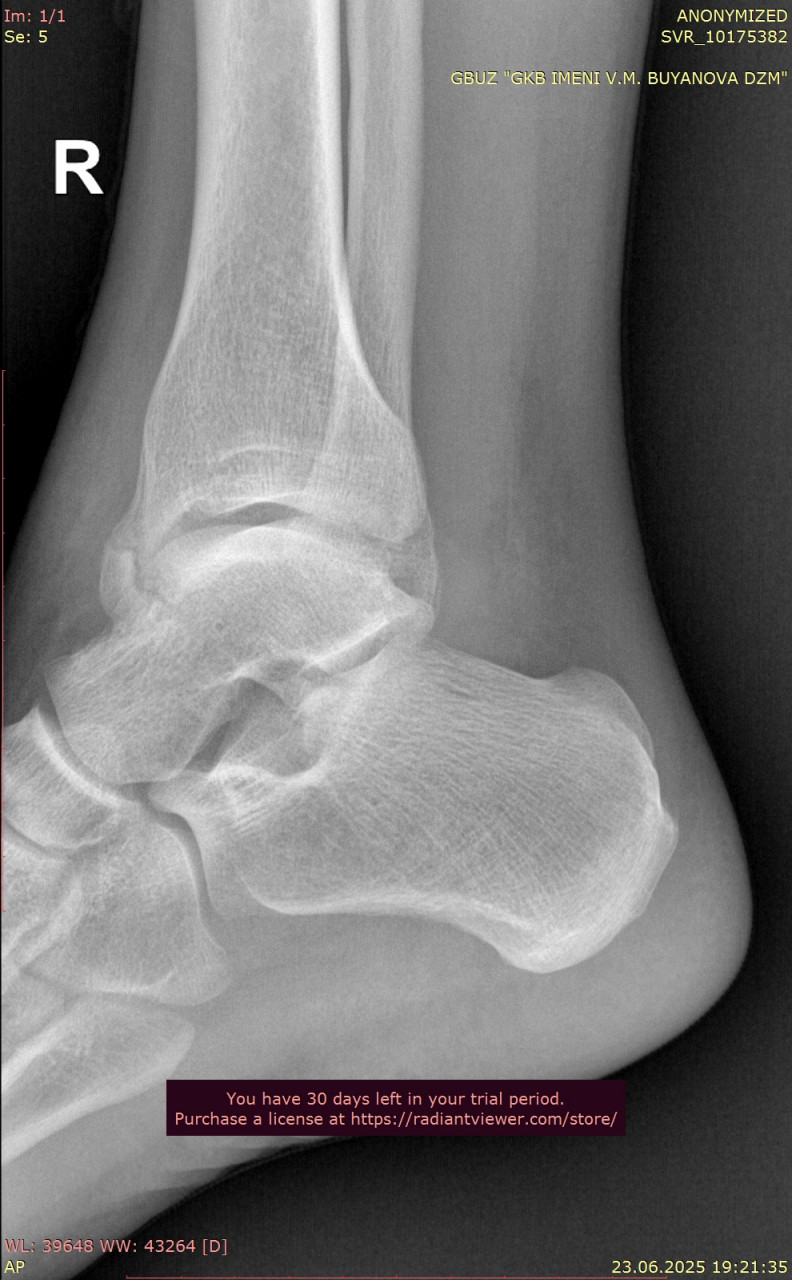

Прикрепляю снимки лодыжки от 23.06.2025, когда был перелом

Сравнивая ваши снимки от 23.06 и 25.08:

- Линии переломов на костях стопы и области голеностопного сустава больше не прослеживаются чётко, видна формирующаяся костная мозоль – это признак заживления.

- Смещения отломков нет, контуры выровнены, что говорит о правильном срастании.

- Для срока 2 месяца после перелома динамика положительная, основные признаки консолидации присутствуют. Обычно к этому времени разрешают постепенную нагрузку, но полное снятие опоры (ходьба без костылей, тростей) должно быть постепенным и согласовано с вашим травматологом.

По поводу артроза, на рентгене действительно заметны начальные изменения в суставах стопы (сужение суставных щелей, небольшие краевые разрастания), но они умеренные и для 38 лет не критичны. Такие изменения часто встречаются после травм и нагрузок, но выраженного деформирующего артроза нет.